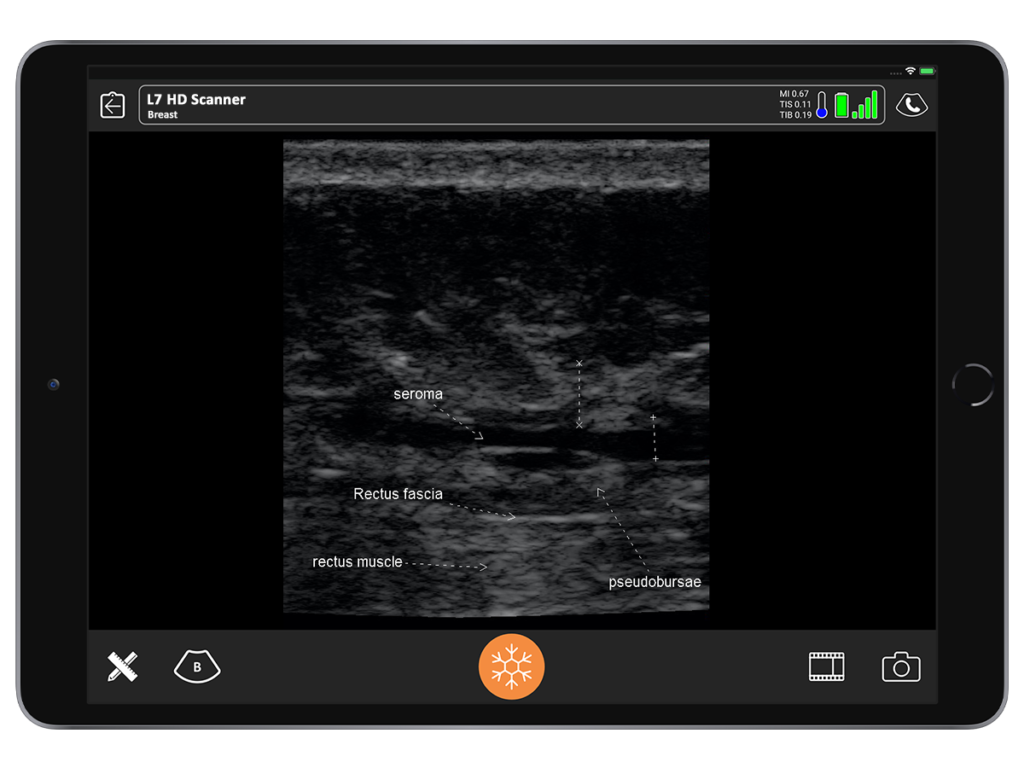

One of the coolest experiences I’ve ever had with ultrasound was being able to clearly see the clinical correlation between what I expected to see and what was actually there. I inherited a patient who had an abdominoplasty 12 to 14 months prior by another surgeon. She had developed a chronic seroma that had been aspirated half a dozen times. A sclerosing agent had been put in to try and stop the fluid buildup. She had both in and out indwelling drains.

When I examined the patient, I noted a huge contour deformity. I knew the plastic surgeon who performed the procedure would not have left this degree of irregularity with liposuction or with the underlying muscle.

When I placed the ultrasound device on the deformity, I could see a black hole that extended all the way up to the area of undermining, from the pubis, around the umbilicus all the way up to the xiphoid. Around that anechoic fluid was thick sclerotic fat. Although I had never seen this, I diagnosed it as a pseudo bursa. I predicted it would look like an orange peel with grungy-looking material on the inside and fluid.

When we saw it in the operating room, it looked exactly as I had seen in the ultrasound. It was the same size. I found it very satisfying.